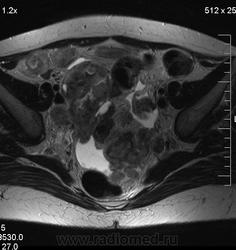

в-целом, cогласен. Карциноматоз тоже есть. Видится еще диффузный аденомиоз матки (задней стенки).

Мне кажется, что есть инфильтрация и передней стенки прямой кишки.